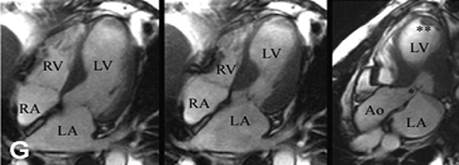

Hình ảnh MRI bệnh Takotsubo